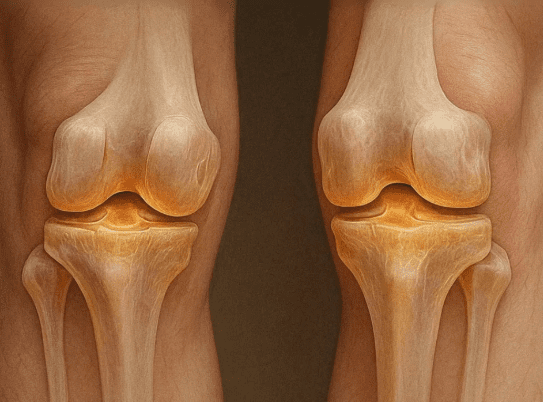

Le collagène est l’une des protéines les plus essentielles de l’organisme. Il constitue la base structurelle des tissus conjonctifs comme le cartilage, les tendons, les os et la peau. Pour la santé des articulations, le collagène assure la souplesse, favorise la mobilité et contribue au maintien de l’intégrité articulaire.

Cependant, avec l’âge, ou si notre alimentation est pauvre en nutriments essentiels, notre production naturelle de collagène commence à diminuer. Cette baisse peut entraîner des raideurs articulaires, des douleurs et, à terme, des affections plus graves comme l’arthrite.

L’usure du cartilage rend les mouvements de base douloureux. C’est pourquoi il est essentiel de maintenir un taux de collagène adéquat pour la fonction et la mobilité des articulations.

Au-delà de son rôle de soutien structurel, le collagène contribue également à la cicatrisation des tissus. Aider l’organisme à maintenir ou à stimuler sa production de collagène peut favoriser la réparation et la résilience des articulations au fil du temps.